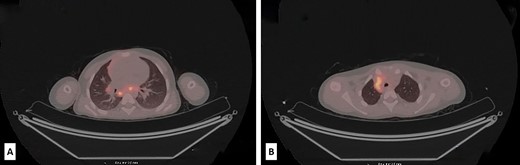

The postoperative course was eventful. Four months later, during the routine follow-up, an abdominal CT scan revealed no residual disease but showed significant lymphadenopathy in the lower abdomen, while PET/CT revealed metabolically active deposits in the retroperitoneal, mediastinal, hilar and neck lymph nodes (Fig. 3A−B). A few suspected small nodes were also found in the left lower lung lobe. Lab tests showed high levels of LDH 548 U/L (range 100–190). Based on the clinical findings and the limited therapeutic options, the tumor board decided to do comprehensive genomic profiling of the tumor. The profiling was performed with the Oncomine Comprehensive Assay Plus (DNA, 498 genes) and Archer Fusion Plex Pan Solid Tumor v2 Panel (RNA, 137 genes) at the University Hospital Basel (Switzerland) (see Acknowledgement).

Low-dose PET/CT scan from the level of upper thoracic aperture revealing enlarged and metabolically active retrocaval and mediastinal lymph nodes, with SUVmax 8.6 and SUVmax up to 6.5 (A). Also, at the level of the carina and subcarinal region metabolically active lymph nodes were seen (SUVmax up to 7.6). In the right hilus, metabolically active lymph node SUVmax up to 3.5 was also observed (B).